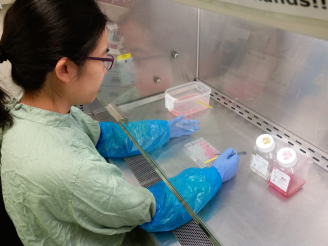

The explant culture system of the human respiratory tract was developed by Professor John Nicholls of HKU Department of Pathology, in conjunction with Dr Michael Chan, Dr Renee Chan, Professor Leo Poon and Professor Malik Peiris at the School of Public Health, in 2005, in order to develop a laboratory based method for studying severe respiratory virus infections with a more faithful replication of disease mechanisms and treatment outcomes in humans. The system is proved to be more effective for the study than alternative experimental methods, such as cell lines grown in culture or experimental animals, as the latter often fail to reproduce the situation in human respiratory tract.

The explant culture system uses respiratory tissues removed from patients undergoing surgery at Queen Mary Hospital, which are normally discarded but are now reserved with ethical approval for the purpose of research. After over eight months of optimization of the study, this system is now accepted by the World Health Organization (WHO) as a model for pandemic risk assessment of animal influenza virus infections, and has also been utilized by biotechnology companies to evaluate potential antiviral compounds. Funding from the Food and Health Bureau, HKSAG and The Research Grants Council, University Grants Committee, has enabled the system to be developed, optimized and maintained.